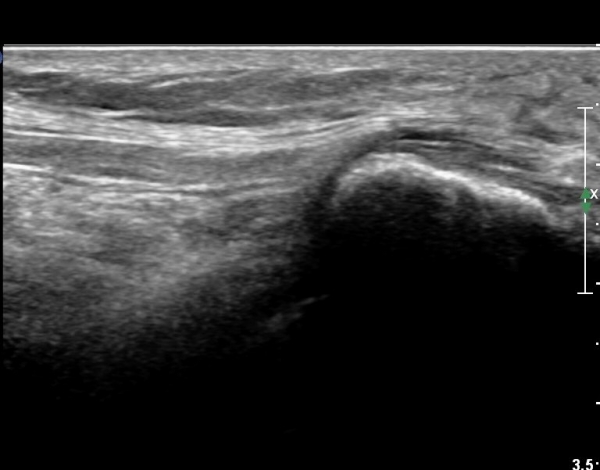

ŽÃËÀÚ¸¦ ¸»´ÜÀ¸·Î À̵¿ÇÏ´Ï À̵ιڱ٠³»Ãø¿¡¼­ ºñ°ñ½Å°æ¿Í °üÂûµÈ´Ù(»çÁø 2).